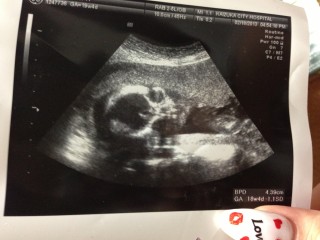

頭の大きさ4.52センチ

胴回り15.49

太もも2.79センチ

重さ274グラム

少し小さめですがほぼ週数通り♪

性別はまだ分かりませんでしたが骨盤の形からみると女の子っぽい!との事でした\(^o^)/